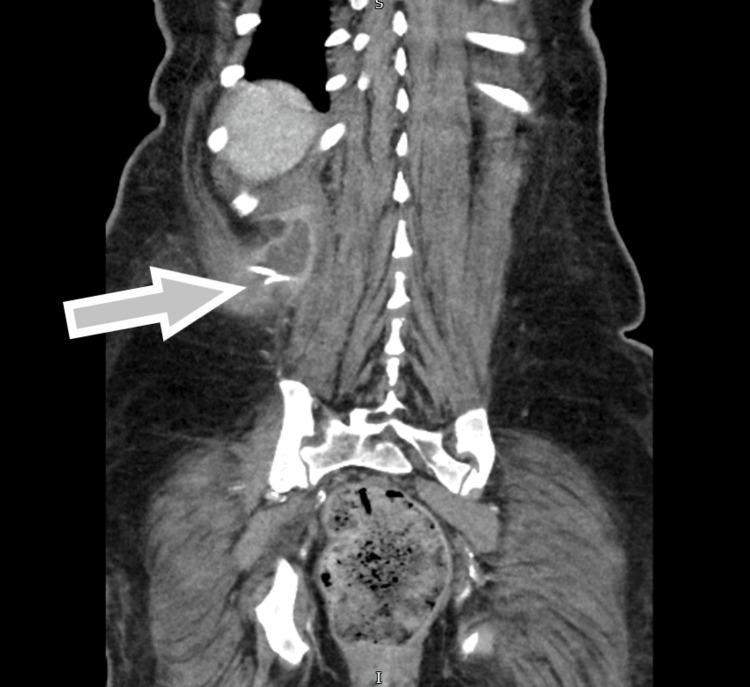

Iliopsoas abscess is a rare infection that presents with a triad of fever, back pain, and hip pain. However, due to the anatomical proximity of the psoas muscle to various structures, an abscess in this region can manifest with nonspecific symptoms, leading to potential misdiagnosis and delayed diagnosis, which can be fatal. We report a case of a 54-year-old female who presented to the emergency department with right-sided flank pain and symptoms resembling lower motor neuron disorder. Initial investigations were inconclusive until an MRI revealed a large retroperitoneal collection in the right perinephric space and iliopsoas muscle, likely of urological origin, with no spinal abnormalities. Intravenous gentamicin was initiated. A subsequent contrast-enhanced CT scan of the abdomen and pelvis confirmed a right posterior perinephric collection. Ultrasound-guided drainage was performed, and a pigtail catheter was placed in situ for continuous drainage along with targeted antibiotics based on culture and sensitivity.

髂腰肌脓肿是一种罕见的感染性疾病,表现为发热、背痛和髋部疼痛三联征。然而,由于腰大肌与各种结构在解剖位置上相邻,该区域的脓肿可能表现为非特异性症状,导致潜在的误诊和诊断延迟,这可能是致命的。我们报告一例54岁女性,因右侧胁腹疼痛及类似下运动神经元疾病的症状就诊于急诊科。最初的检查结果不明确,直到磁共振成像(MRI)显示右肾周间隙和髂腰肌有一个大的腹膜后积液,可能源于泌尿系统,且无脊柱异常。开始静脉注射庆大霉素。随后的腹部和盆腔增强CT扫描证实右肾后有积液。进行了超声引导下引流,并置入一根猪尾导管进行持续引流,同时根据培养和药敏结果使用针对性抗生素。